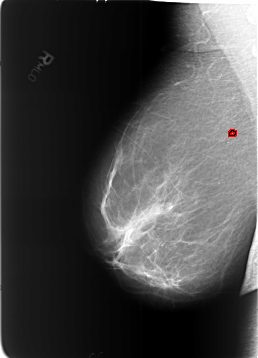

FILE: B_3453_1.RIGHT_MLO.OVERLAY

TOTAL_ABNORMALITIES 1

ABNORMALITY 1

LESION_TYPE CALCIFICATION TYPE SKIN DISTRIBUTION REGIONAL

ASSESSMENT 2

SUBTLETY 3

PATHOLOGY BENIGN_WITHOUT_CALLBACK

TOTAL_OUTLINES 1

BOUNDARY

FILE: B_3453_1.RIGHT_CC.OVERLAY